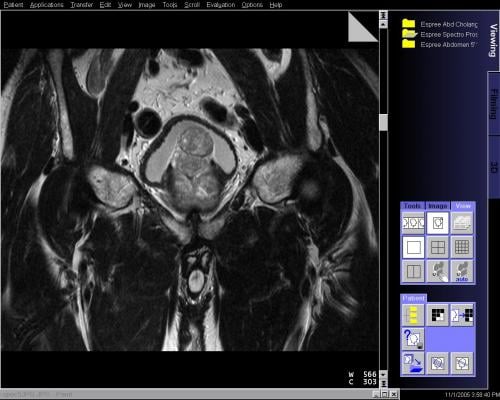

The research was conducted at UCLA, and Chamie's team found that radiation therapy was the most common treatment at 58 percent, followed by radical prostatectomy (a surgical procedure to remove the prostate) at 19 percent. Other treatments trailed at 10 percent, including watchful waiting (where doctors wait and see if cancer progresses before treating it) and active surveillance (when patients undergo routine biopsies, blood tests and magnetic resonance imaging [MRI] to determine if cancer is progressing and undergo active treatment).

"Men fighting this disease don't always need radiation or surgery as their only choice," said Chamie. "As we find more reports demonstrating the safety and efficacy of active surveillance, I hope patients and physicians look to this as the first treatment option for low-risk and indolent disease. Here at UCLA, I am proud to say that we have a robust active surveillance program that utilizes MRI and targeted biopsies to monitor and survey these indolent tumors."